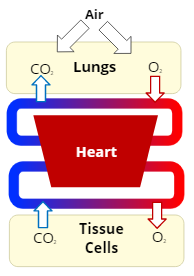

Respiration

the exchange of oxygen and carbon dioxide in the body

External Respiration

the exchange of the gases, oxygen and carbon dioxide, between the air in the lungs and the bloodstream

Internal Respiration

the exchange of the gases, oxygen and carbon dioxide, between the bloodstream and cells in the body's tissues

Oxygenation

the process of supplying oxygen to the body’s tissue cells